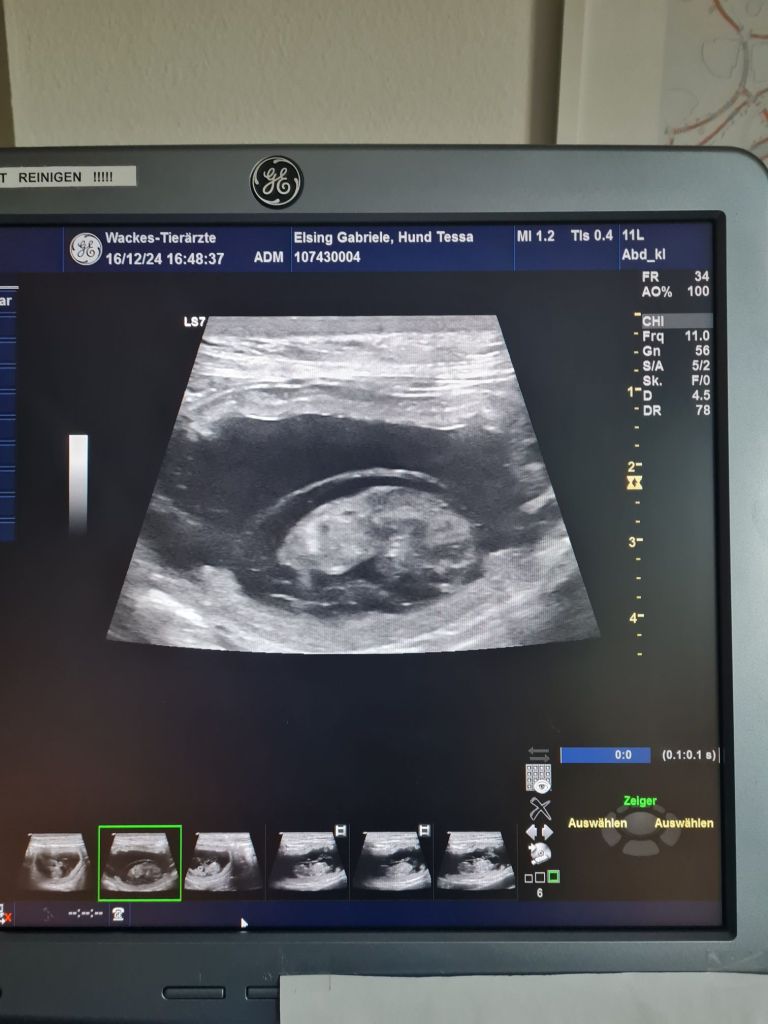

16.12.2024 noch circa 4 Wochen bis zum Wurf. Fötus 2½cm groß